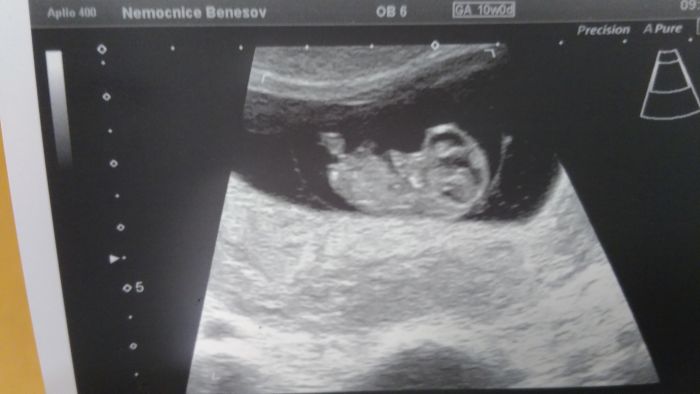

My dnes koncime 12tt..zitra 12+1..tp mame 24.10...ale pocitam ze bude listopadek..nu a na utz.vychazelo o 2dny mene..

Utz..ze 7tt..kvuli tomu zda bije srdicko..ted jdeme 12teho..uz se s tatkou tesime...dnesni krece nas oba vydesili..uz nejsem nejmladsi..?